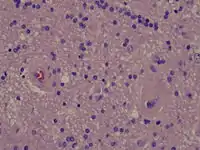

Radiation necrosis

- Brain Radiation Necrosis

- Low power microscopy

- Intermediate power microscopy

- High power microscopy